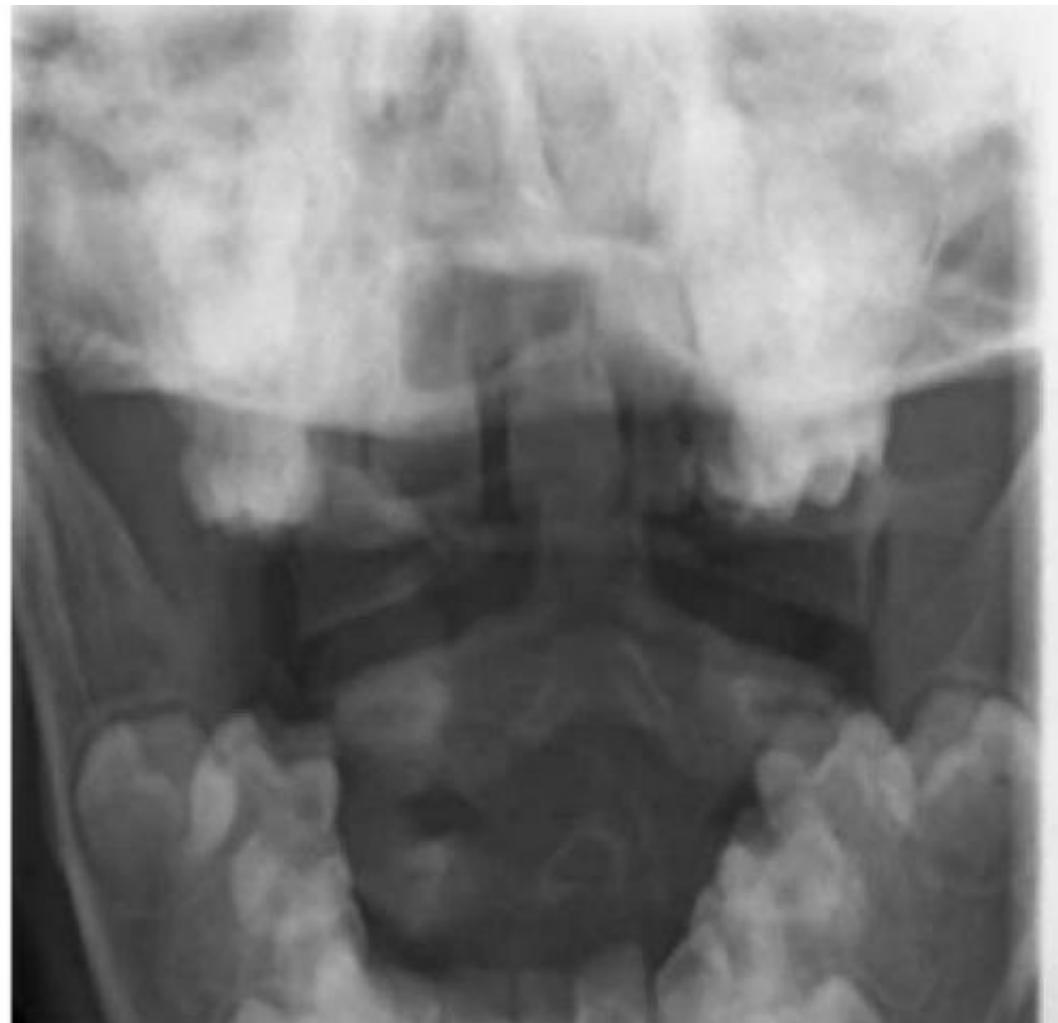

C-Spine X-ray

- Views:

- Lateral View: Must show C1 down to the C7-T1 junction.

- AP View.

- Odontoid (Open Mouth) View: Used to visualize C1 and C2 (especially the dens).

- Pathology:

- Odontoid Fracture (C2): Seen on the open mouth view.

- C2 Fracture (Hangmanโs fracture) can be seen on the lateral view.